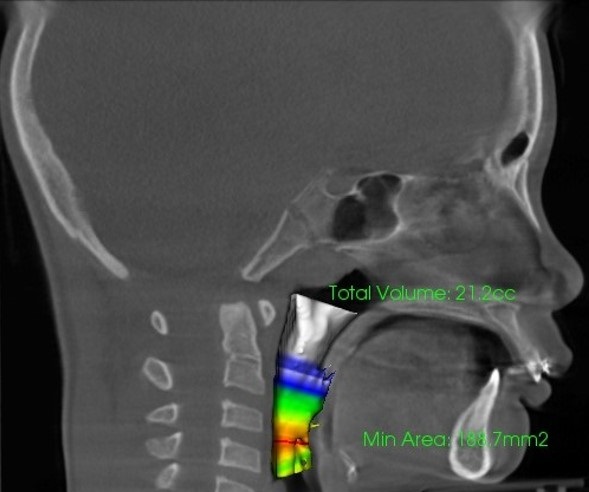

【気道容積の測定】(左:治療前8,1cc 右:治療経過21,2cc)